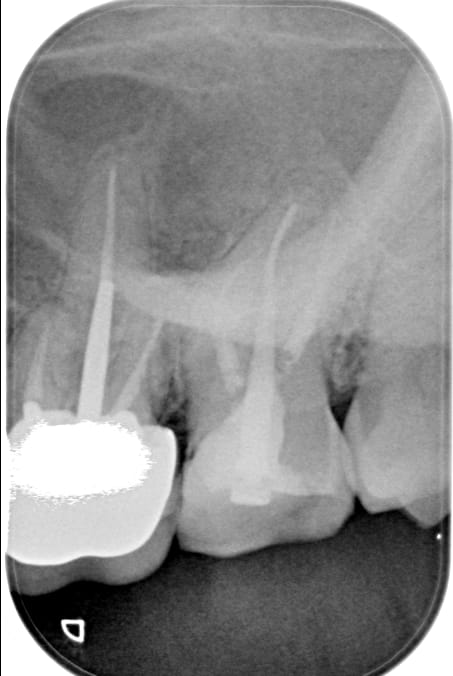

J'ai réalisé en Mars 2016 une CCM sur 26 que j'ai dévitalisée suite à une pulpite, chez une femme de 45 ans très active , voire overbookée ( grosse responsabilité pro, 3 enfants, 3 portables etc etc... ) avec peu de hauteur occlusale.

Cette céram se descellait tous les 3 mois malgré mes recherches pour résoudre le problème : prématurité et occlusion étudiée, collage différent etc etc

Comme j'avais, il y a qq années dévitalisée la 27 et sa reconstitution coronaire s'étant légerement cassée et dégradée , je me suis décidée à démonter la CCM sur 26 et à réaliser 2 Full zircones solidarisées sur 26 et 27 avec inlay core sur les 2...

Je me suis dit que le descellement de 26 et la fracture du morceau de 27 étaient dû à son peu de hauteur occlusal !!!

Et là c'est pire !!! Je n'ai pas réussi à trouver une occlusion qui lui convienne... Mes 2 full zircone sont lisses comme une patinoire tellement j'ai du les meuler..

mais si tu avais 1 photo mes visions pourraient revenir .

" Au rdv du soir je les règle en légère sous occ, la patiente se trouve bien et dès le lendemain, elle m'appelle pour me dire qu'elle est en sur occlusion !! "

on va partir la dessus si tu n as pas de photos .